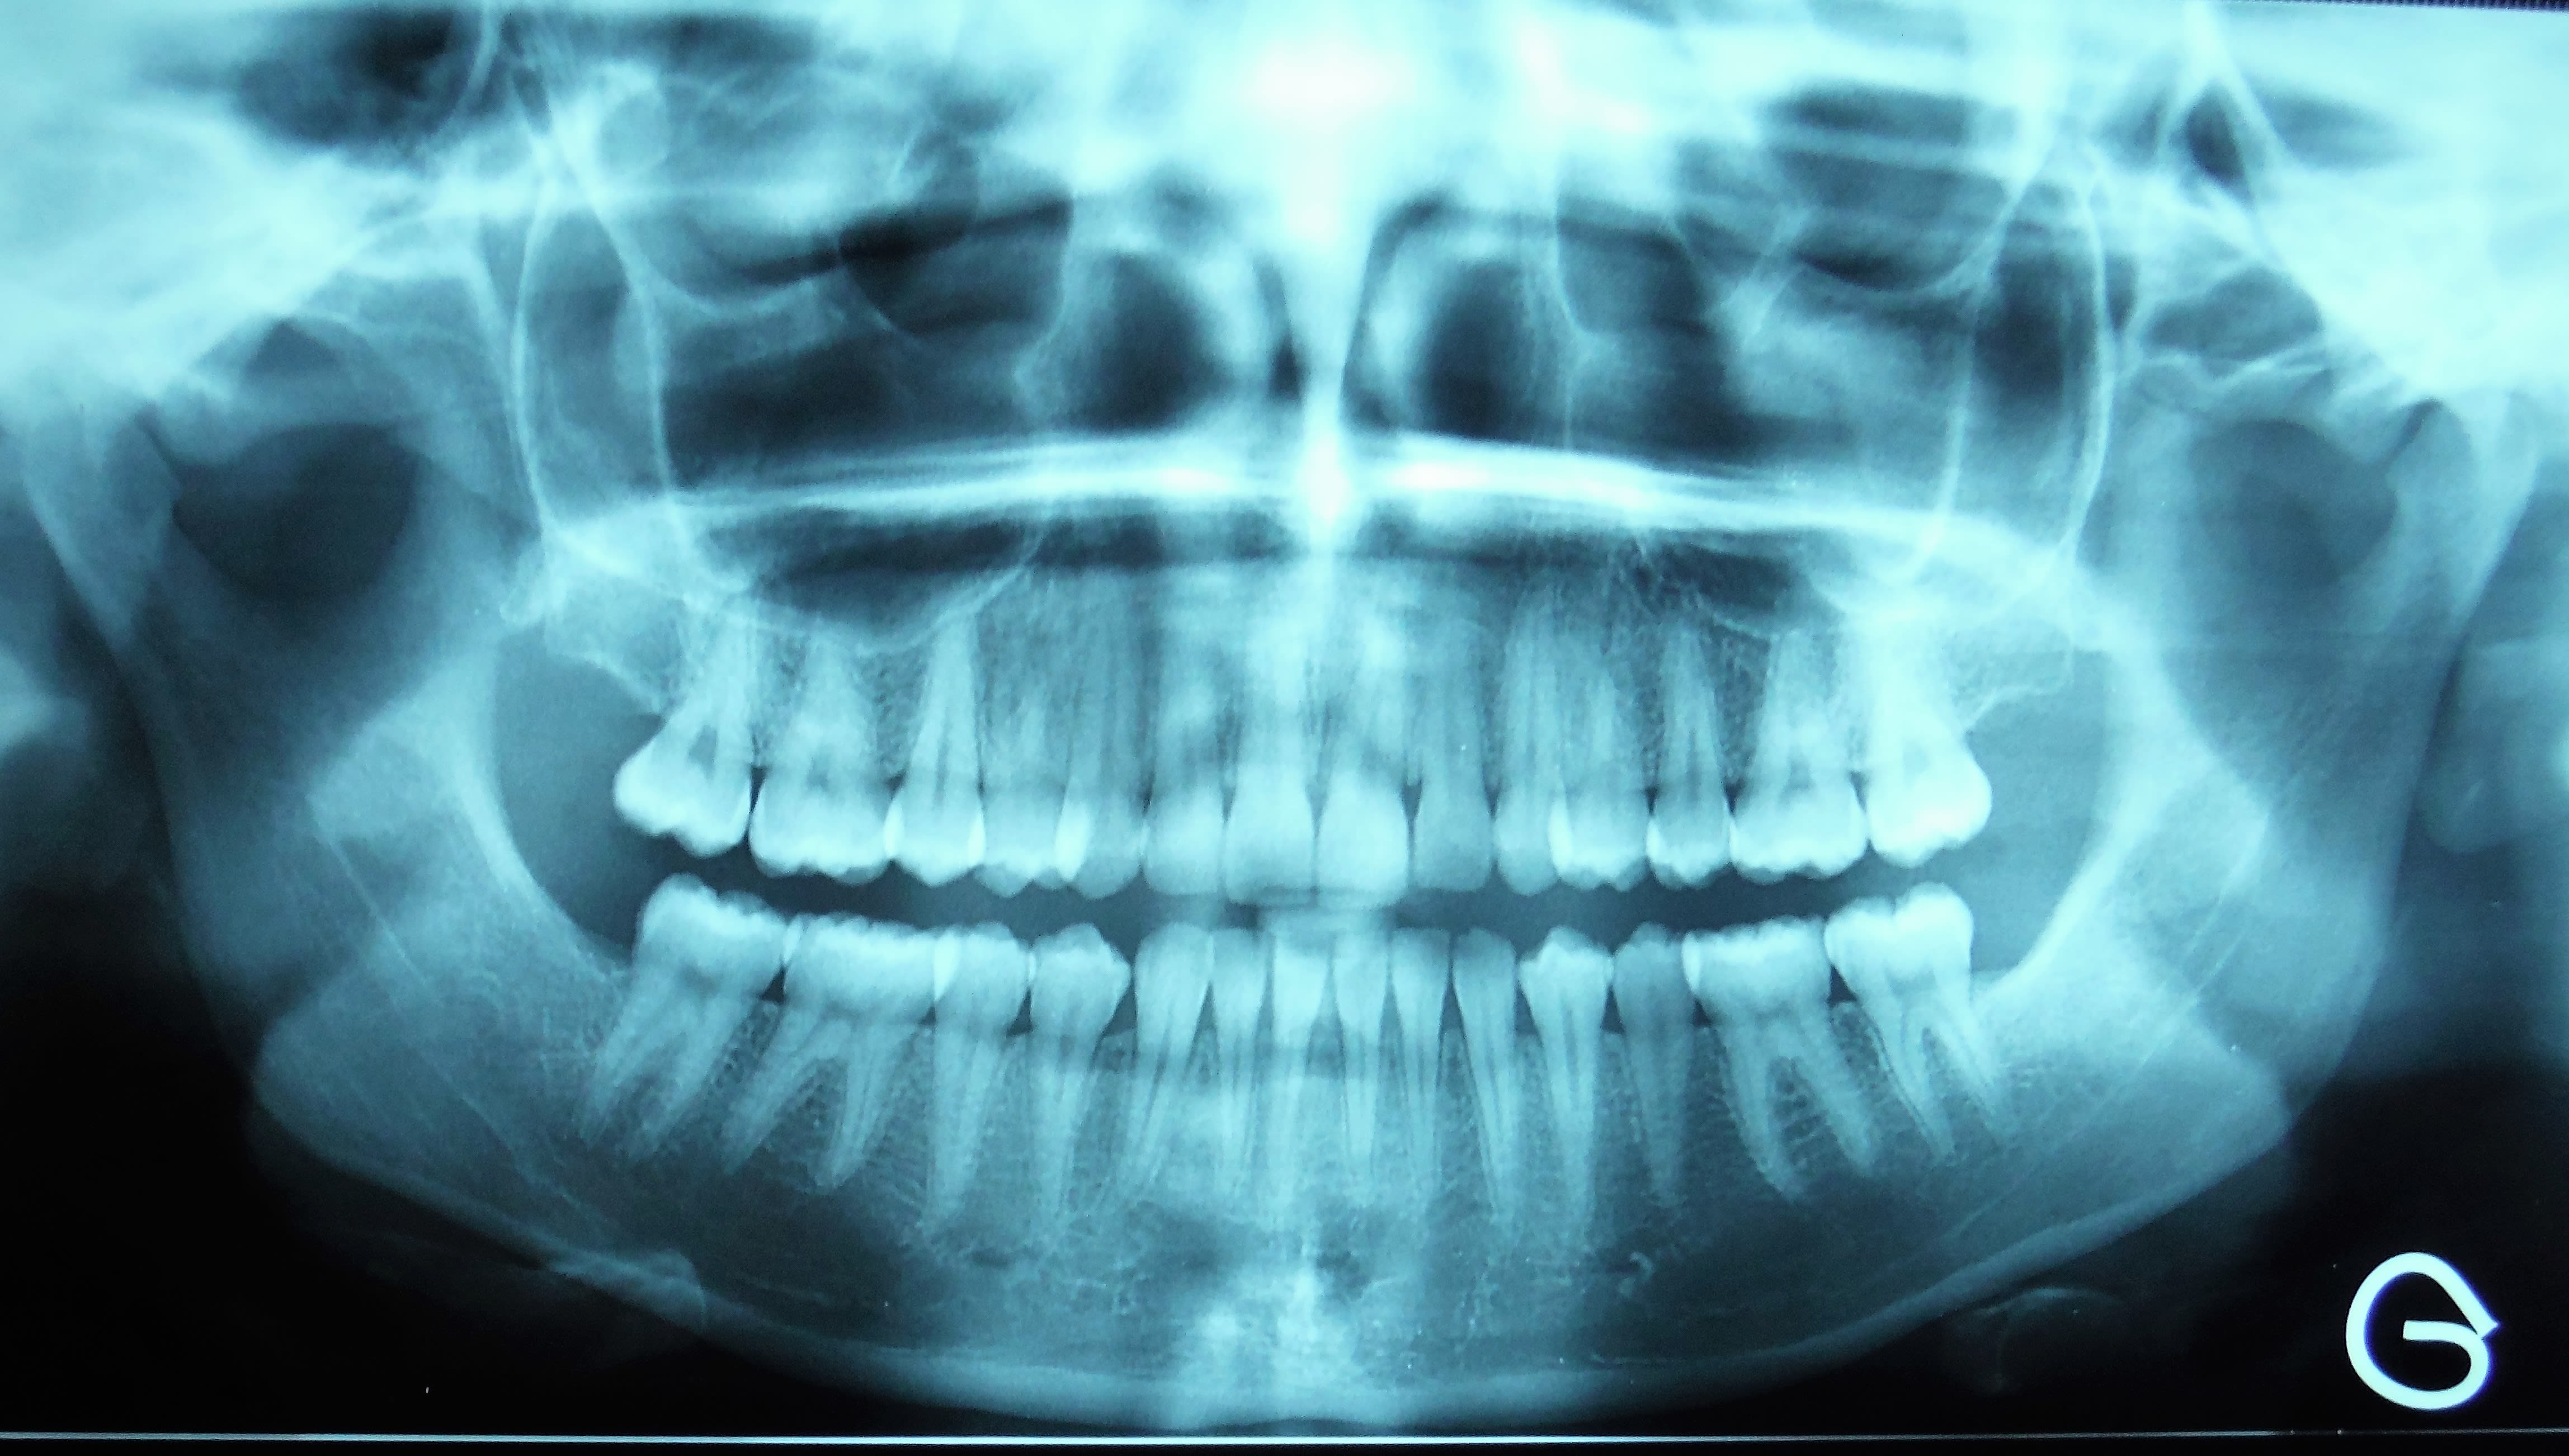

Patiente de 16 ans, pas d'antécédent médical.

Traitement orthodontique terminé il y a 2 ans, avulsion des DDS mai 2015.

Douleur fin août coté droit diagnostiqué dans un premier temps comme une otite (Ciflax en ttt local), pas d'amélioration, la douleur est maintenant localisée face interne de l'angle goniaque droit, plus importante le matin au réveil et en fin de journée, mais présente toute la journée, c'est le motif de la consultation.

Limitation de l'ouverture: deux doigts, pas de déviation à la fermeture.

sans commentaire.

Ah si! 64 ans... et 41, 31 HS...

Lui 59 ans, 41 HS, c'est la semaine!!! les photos ne sont pas tops :-(